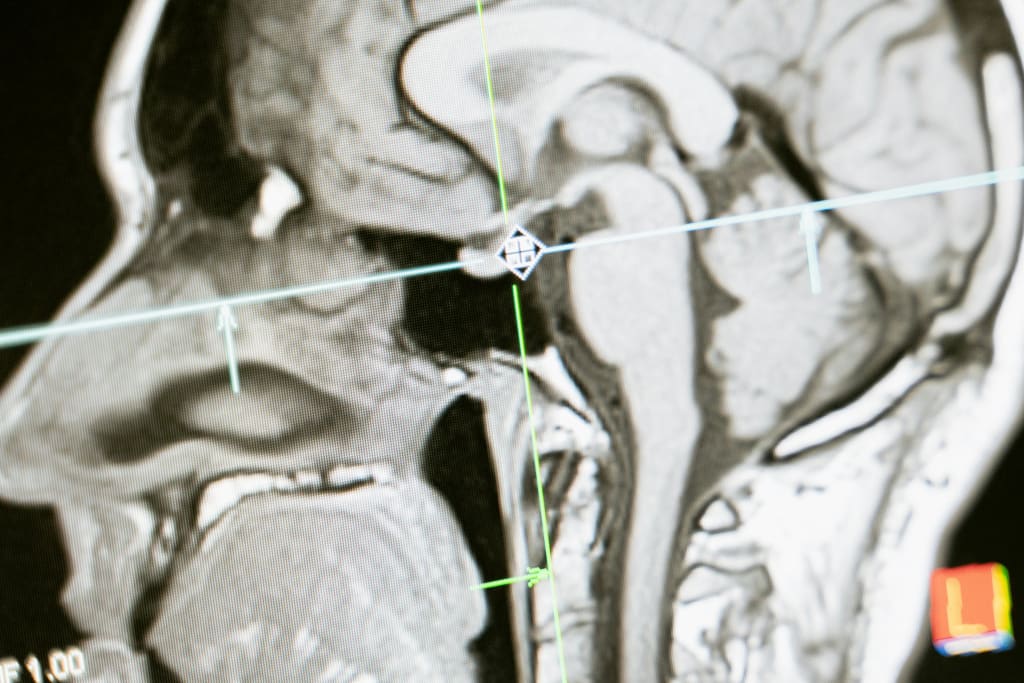

The Leeds research group applied this creative gadget to concentrate on glioblastoma (GBM), the most deadly type of mind malignant growth, north of a 72-hour time span. With roughly 3,200 individuals determined to have GBM every year in the UK, the sickness represents an extreme danger to patients.